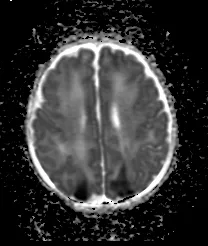

Cardiac MRI Study

The Cardiac MRI study uses advanced imaging to assess brain injury associated with severe congenital heart disease and its treatments, as well as long term neurodevelopmental outcome of affected children.

The Cardiac MRI study has been ongoing since 2002. The goal is to understand brain development and risks of brain injury in babies with congenital heart disease. The results so far include:

Newly acquired brain injury is as common BEFORE surgery as after:

This is surprising because prior to this finding many people assumed that the period of greatest risk to the baby occurred during surgery when support with heart/lung bypass is needed to accomplish the repair.  Clearly two decades of advances in surgical technique and cardiopulmonary bypass have made surgery safer and more effective!  Now our challenge is to extend brain protection into the periods before and after surgery, as well as during surgery.

Acquired injuries most commonly take the form of small injuries to the developing white matter:

This observation was very surprising because white matter injury had previously been thought to only occur in newborns born prematurely.  This led us to ask the question:  ‘Is brain development somehow delayed in newborns with congenital heart disease?’

Brain development is delayed in newborns with congenital heart disease:

This has been the most surprising and influential study result to date.  This finding was reported inThe New England Journal of Medicine and led to many newspaper articles and TV coverage.  This finding has since been validated by other investigators.  Brain development begins to slow prenatally in the third trimester before birth.  The delay in brain development is mild (~ equivalent to being born one month premature – e.g. 34-36 weeks instead of 40 weeks gestation).  As with premature newborns, evidence suggests that infants with CHD have potential for recovery of developmental milestones as they grow up, with improvements noted during infancy and childhood as they are followed with repeated testing.

Moderate to severe white matter injury predicts motor impairment in infancy:

This is our most recent publication in the Journal of American College of Cardiology and has been influential in changing clinical practice for our babies with congenital heart disease.  For the first time, our study demonstrates the benefits in obtaining brain MRI in the newborn period in order to identify the highest-risk patients for neurodevelopmental impairment.

Currently we hypothesize that delayed brain development may put newborns with CHD at risk of white matter injury around the time of surgery.  ‘White matter’ includes the connection between brain cells (neurons or ‘grey matter’) and the cells that produce ‘myelin’ to support and insulate the neurons.  We are focused on identifying interventions or medications to prevent any brain injury around surgery.  Selecting these interventions would not be possible without the information we have gathered from our study babies to date.